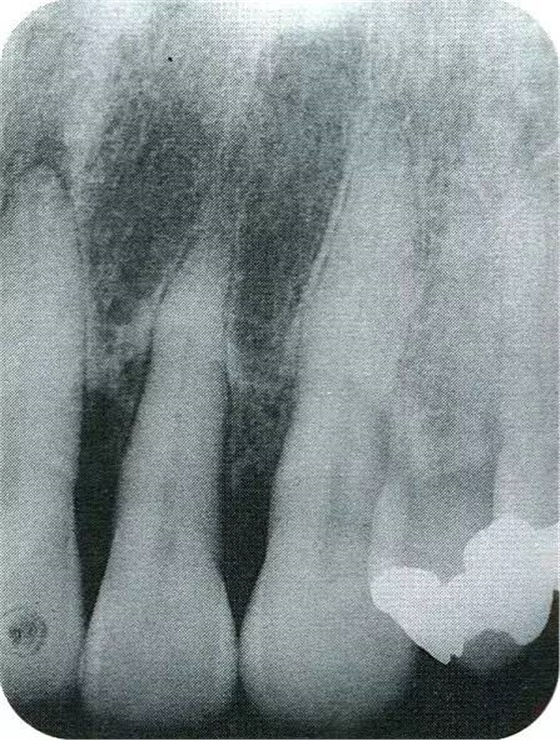

▲圖7-7術(shù)前,術(shù)后的x片。確認(rèn)出現(xiàn)骨再生,牙槽嵴硬線。